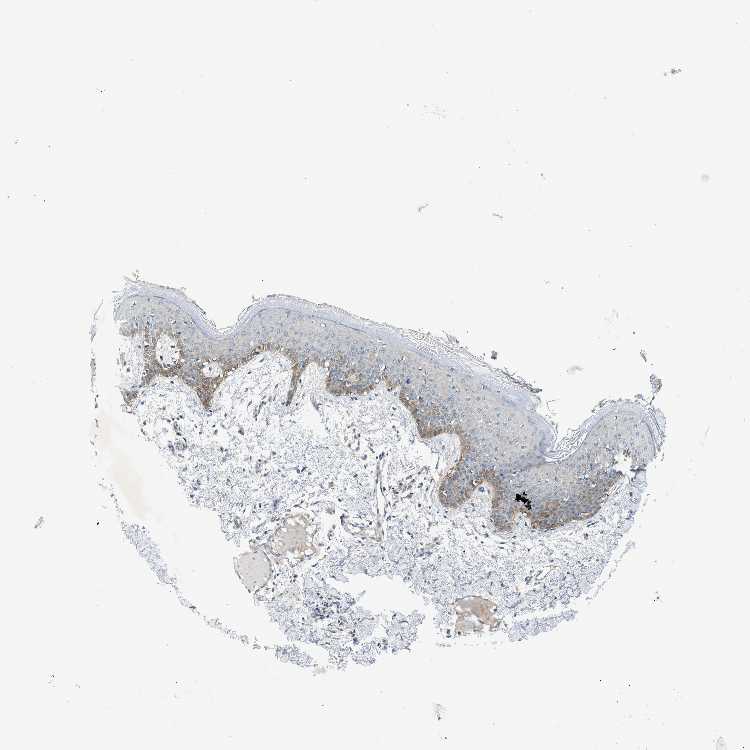

SKIN 1 - Antibody stainingi

Antibody staining in the annotated cell types in the current human tissue is reported as not detected, low, medium, or high, based on conventional immunohistochemistry profiling in selected tissues. This score is based on the combination of the staining intensity and fraction of stained cells.

Each image is clickable and will lead to virtual microscopy that enables deeper exploration of all samples and also displays staining intensity scores, fraction scores and subcellular localization as well as patient and tissue information for each sample.

Antibody HPA016930

Langerhans Not detected

Fibroblasts Not detected

Keratinocytes Not detected

Melanocytes Not detected

SKIN 2 - Antibody stainingi

Epidermal cells Medium